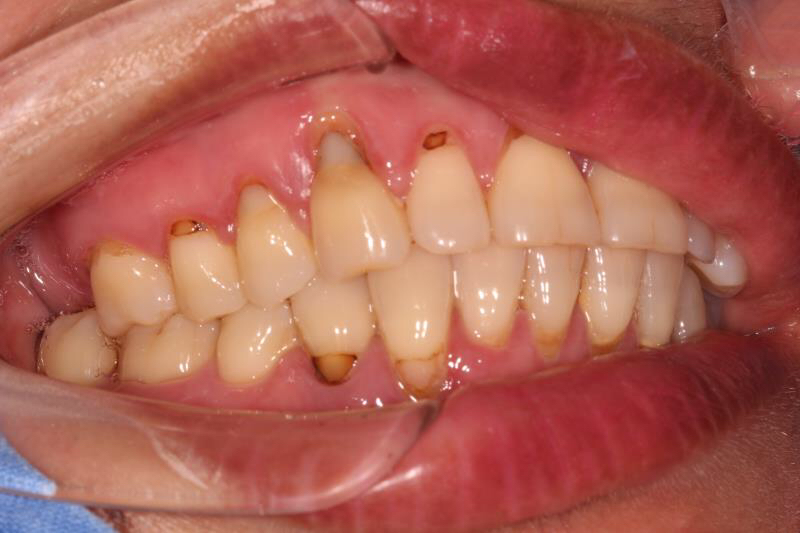

今天给大家分享的病例是一位中年女性,17缺失,由于长时间未修复,47伸长,留给17修复的空间不足。

老卢给她的治疗方案是:17种植修复,47根管治疗后截冠、高嵌体修复。这样可以最大限度的增加患者的咀嚼效率。